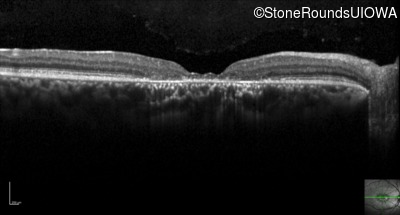

Optical Coherence Tomography - Left - 20/100

Exemplar / OCT Stack

Optical Coherence Tomography - Left - 20/125 +1

Optical Coherence Tomography - Left - 20/100 -1

Optical Coherence Tomography - Left - 20/125